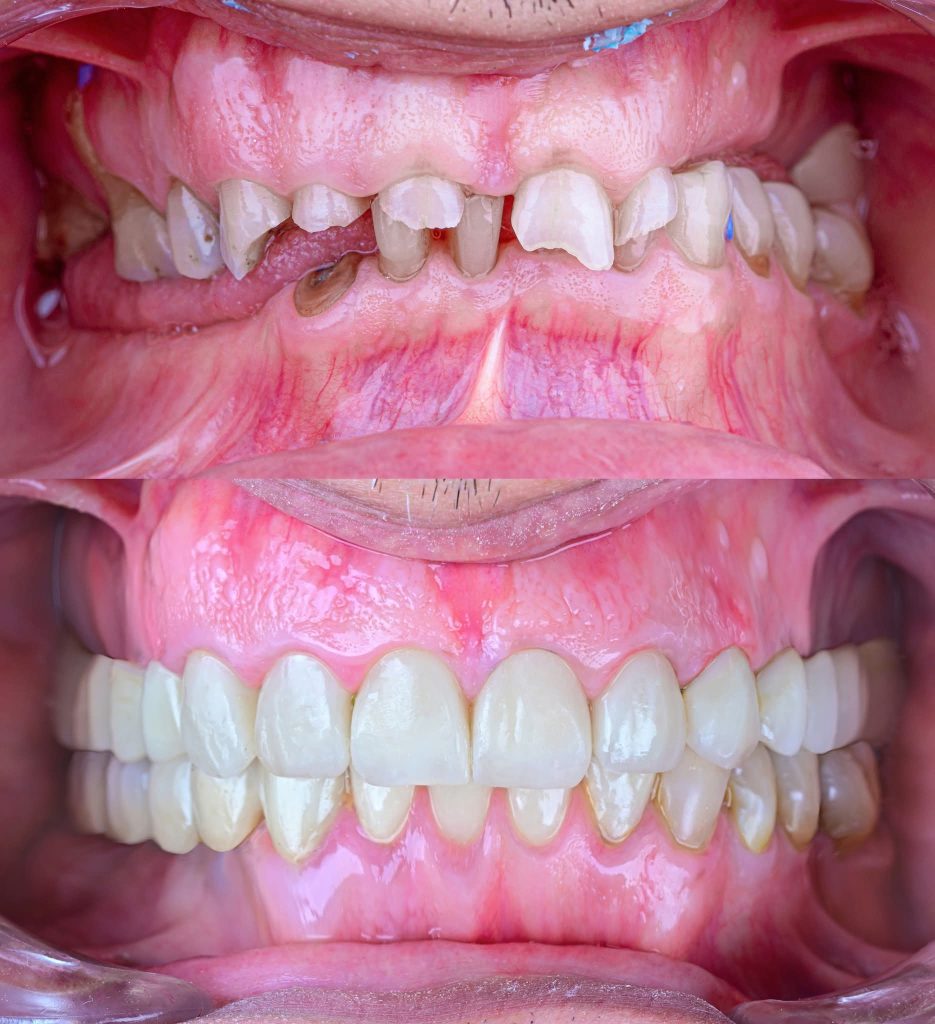

After almost 4 Years Follow-Up.

I am revisiting this Full Mouth Rehabilitation case, which was my first published case in this group.

The patient has now been under follow-up for nearly 4 years and remains very happy and comfortable.